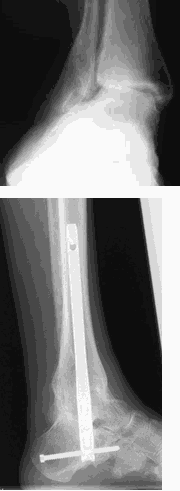

Severe ankle and foot deformity

When left unchecked the poor foot position can sometimes lead to the ankle becoming unstable and potentially arthritic. When arthritis and severe deformity affects both the foot and ankle, this often fails to respond to footwear changes and bracing.

Given these findings, a major fusion of the foot and ankle is often required. The model shows a nail used to fuse the ankle and foot into a neutral position. Whilst this obliterates movement patients can compensate to a degree in the smaller joints of the foot assuming these are not too arthritic.

Post-surgery patients can walk in an orthopaedic shoe with a rocker type sole to provide the movement that would normally be available at the ankle joint.